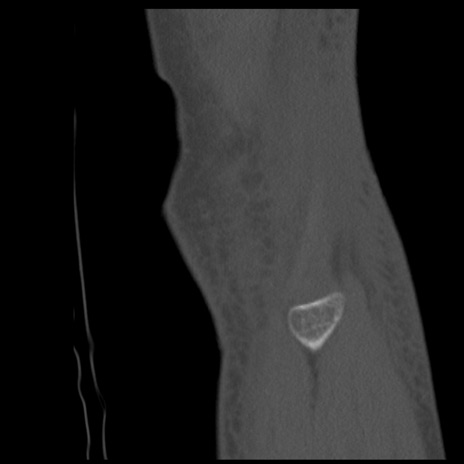

症例28 右膝関節CT(矢状断像)

右膝関節CT

横断像